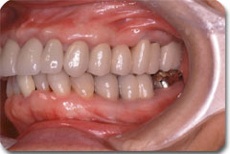

かみ合わせ治療前の状態です